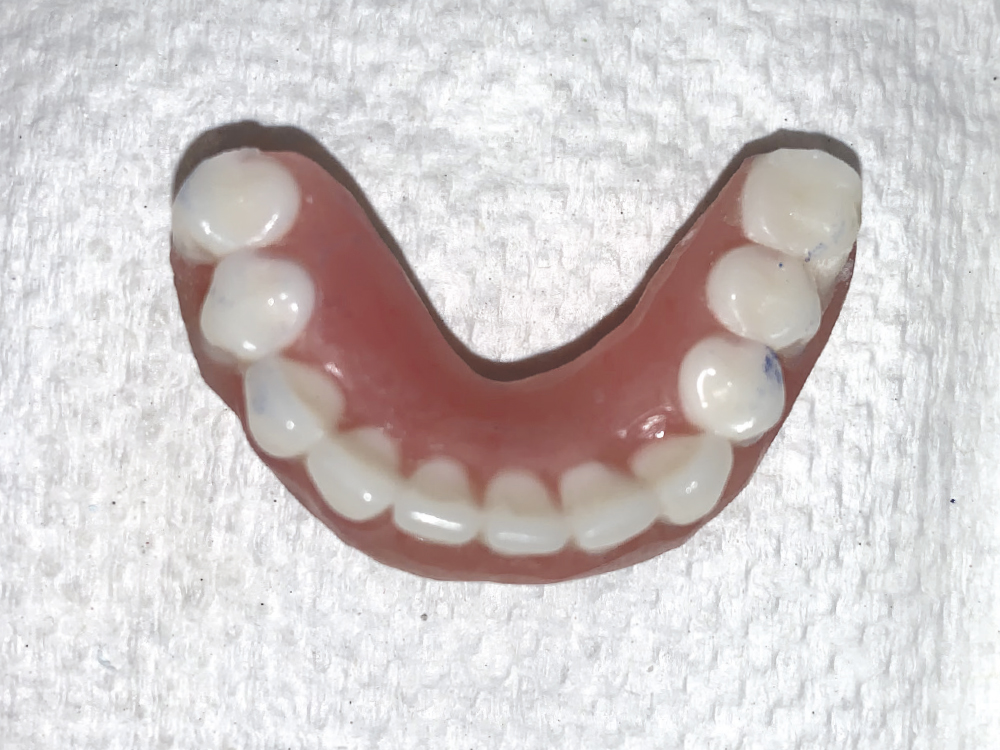

The flanges of the denture were removed, and the distal portion of the denture prosthesis was trimmed slightly posterior to the distal-most implant abutment and attachment.

Occlusal view of the conversion of the original denture to an attachment-retained Locator Fixed appliance.

Figure 12: Occlusal view of the conversion of the original denture to an attachment-retained Locator Fixed appliance.

In this fashion, the denture modification closely resembled that of a conventional All-on-X format, other than having limited distal cantilever of the prosthesis. The appliance was polished with conventional pumice and acrylic polishing material.

Green Locator Fixed attachments replaced black processing attachments following the protocol for a four-implant Locator Fixed case.

Figure 11: Green Locator Fixed attachments replaced black processing attachments following the protocol for a four-implant Locator Fixed case.